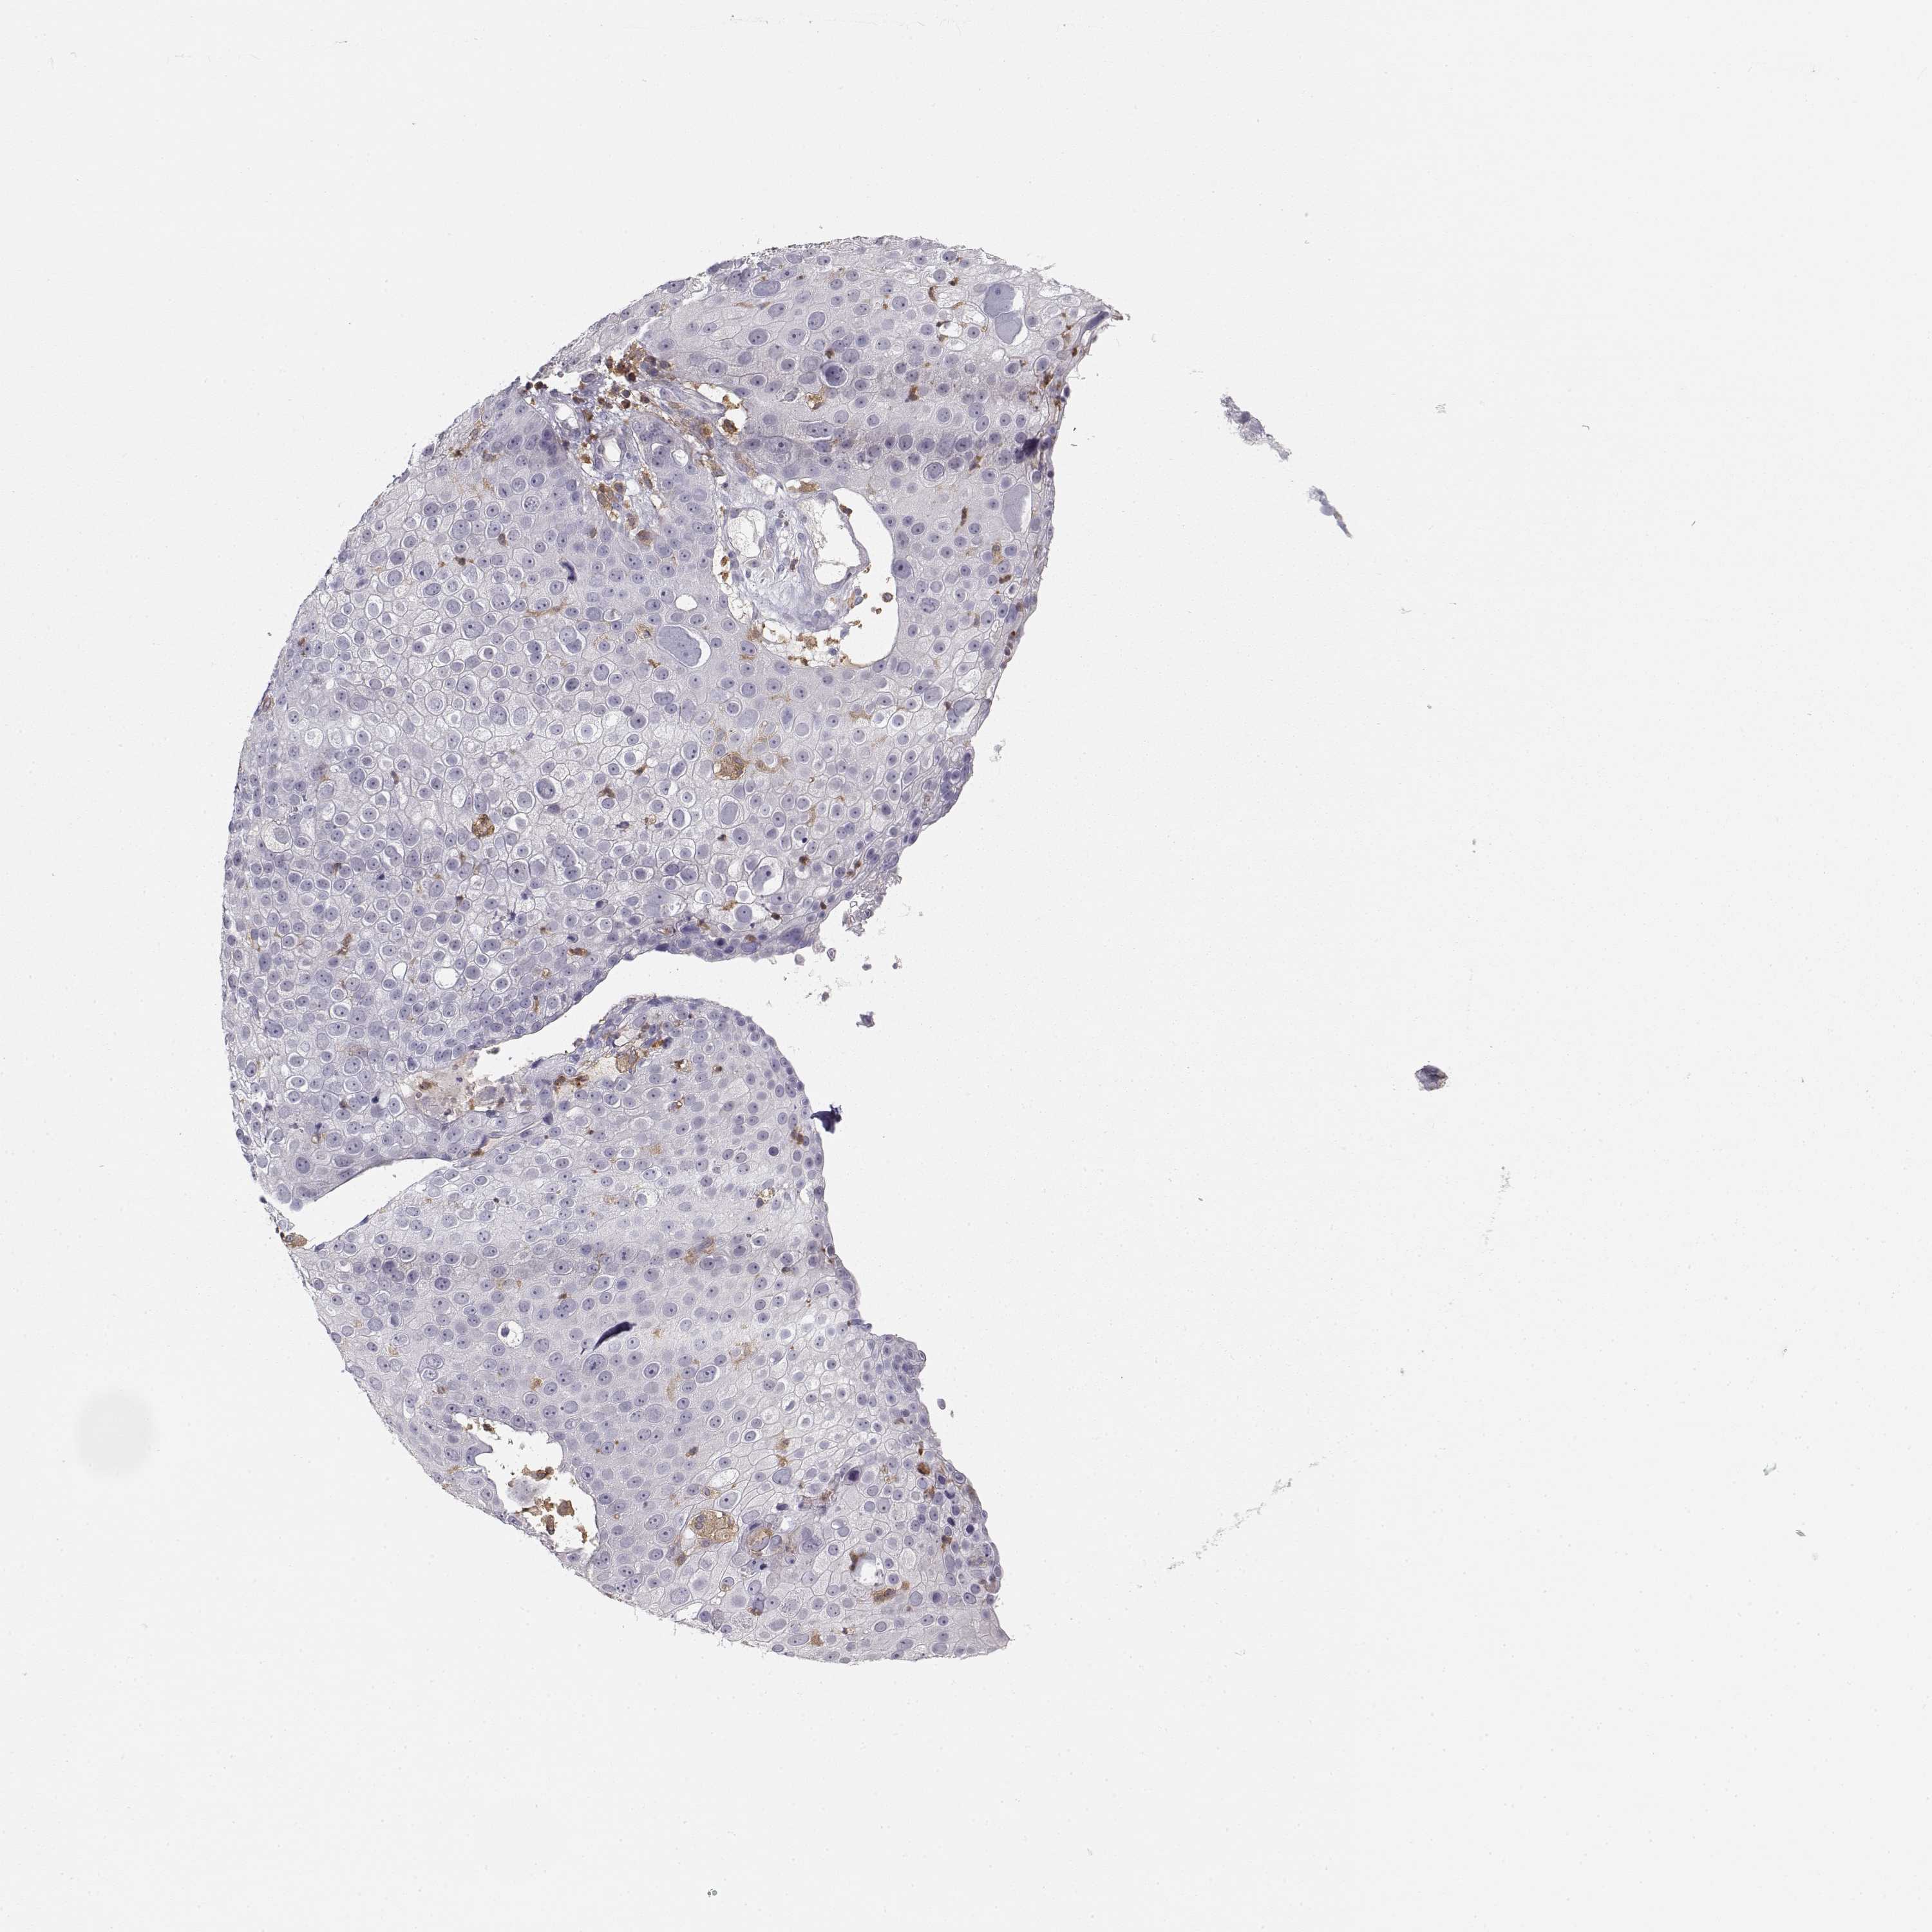

SKIN CANCER - Protein expressioni

A mouse-over function shows sample information and annotation data. Click on an image to view it in a full screen mode. Samples can be filtered based on level of antibody staining by selecting one or several of the following categories: high, medium, low and not detected. The assay and annotation is described here.

Each image is clickable and will lead to virtual microscopy that enables deeper exploration of all samples and also displays staining intensity scores, fraction scores and subcellular localization as well as patient and tissue information for each sample.

Antibody HPA001864

Staining

High

Medium

Low

Not detected

Intensity

Strong

Moderate

Weak

Negative

Quantity

>75%

75%-25%

<25%

None

Location

Nuclear

Cytoplasmic/membranous

Cytoplasmic/membranous,nuclear

Squamous cell carcinoma, NOS

Basal cell carcinoma